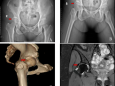

一名患儿因意外外伤导致骶髂关节分离,该部位解剖结构复杂,螺钉置入时稍有偏差便可能损伤周围神经等组织,影响运动功能。机器人导航系统通过术中三维重建数据,精准规划螺钉植入路径,术中实时导航定位,将螺钉精准送达预定位置,整个手术创伤小、出血少,患者康复快。

No.2 股骨头骨骺滑脱

股骨头骨骺滑脱是儿童青少年较少见的髋关节疾病,若不及时治疗,可能导致股骨头缺血坏死、髋关节畸形等严重后果。借助机器人的高精度导航优势,术中无需大面积显露组织,即可完成螺钉精准固定,最大限度保留髋关节正常结构与功能,避免股骨头缺血坏死。